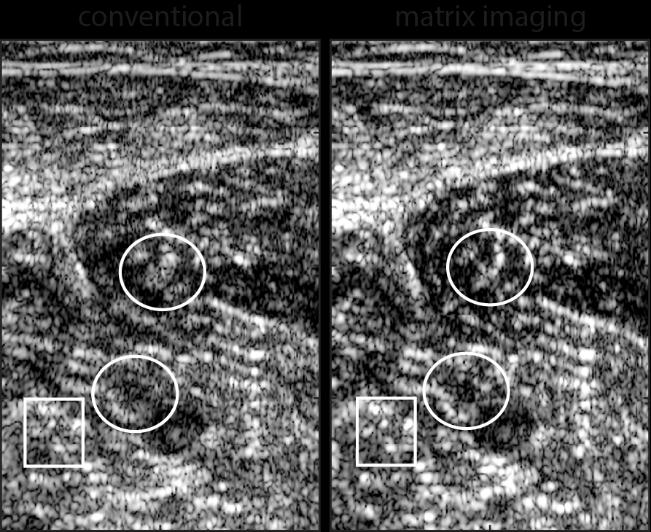

image:Ā Conventional and matrix ultrasound images of a volunteer's calf. Matrix correction of aberrations reveals structures that were previously invisible or had poor resolution in a conventional ultrasound (especially in the areas inside the white lines)

In conventional ultrasounds, variations in soft tissue structure distort ultrasound wavefronts. They blur the image and can hence prove detrimental to medical diagnosis. Researchers at the Institut Langevin (CNRS/ESPCI Paris-PSL)* have developed a new non-invasive ultrasound method that avoids such aberrations. In an article published in the journal PNAS** on 10 June 2020, the scientists showed how this method can subtly compensate for the distortions that a focused wave undergoes as it travels through the studied tissue, with an ideal resolution and contrast optimized for each pixel in the image. This approach can be extended to any type of wave, and can be controlled by a multi-sensor network. Applications range from biomedical diagnosis to optical microscopy, detection of cracks in industrial materials, and the monitoring of volcanoes and fault zones in geophysics.